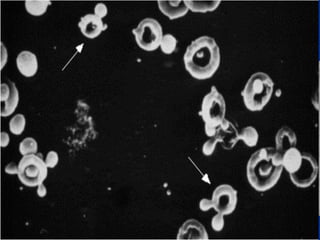

Oval body (Thể bầu dục)

Tế bào biểumô đường sinh dục Tế bào biểu mô ống thận Oval body (Thể bầu dục) Tinh trùng

• #42 Bản chất trụ niệu được thành lập từ protein ống thận (Tamms Horsfall), kết tụ các loại tế bào bất thường đi ngang qua. Nếu đó là hồng cầu, ta gọi là trụ hồng cầu, nếu là bạch cầu, ta gọi là trụ bạch cầu, nếu là tế bào biểu mô ống thận ta gọi là trụ tế bào biểu mô. Nếu là mỡ, ta gọi là trụ mỡ. Nếu không có tế bào nào, ta gọi là trụ trong. Tùy theo thời gian lưu lại các trụ tế bào biểu mô trong ống thận mà chúng ta có nhiều tên gọi khác (trụ hạt, trụ hạt thô, trụ hạt mịn, trụ hạt nâu bùn, trụ rộng, trụ sáp)